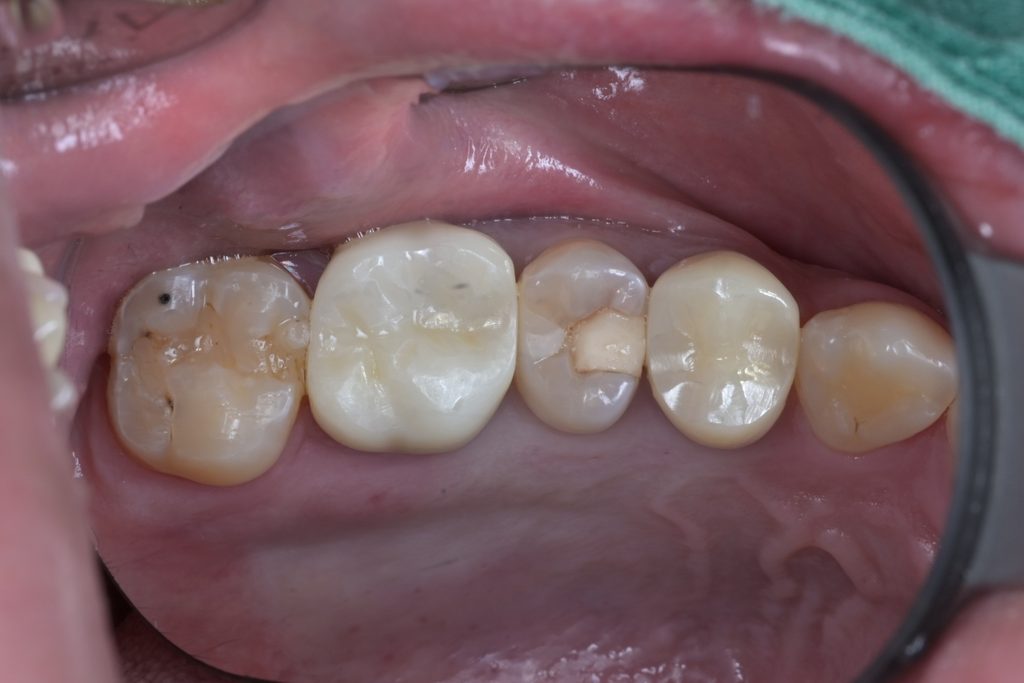

오늘 소개드릴 케이스는 왼쪽 위 작은어금니(제2소구치, #25)에 깊은 충치가 발생하여 내원하신 환자분입니다. 육안으로도 확인되는 충치 병소가 있었으며, 치료 과정에서 예상치 못한 치수 노출이 발생했습니다.

환자분은 특별한 통증 증상 없이 내원하셨으며, 방사선 검사 결과 치근단에 병소는 관찰되지 않았습니다. 다만 우식이 치수에 매우 근접해 있어 치료 중 치수 노출 가능성을 염두에 두고 신중하게 접근했습니다.